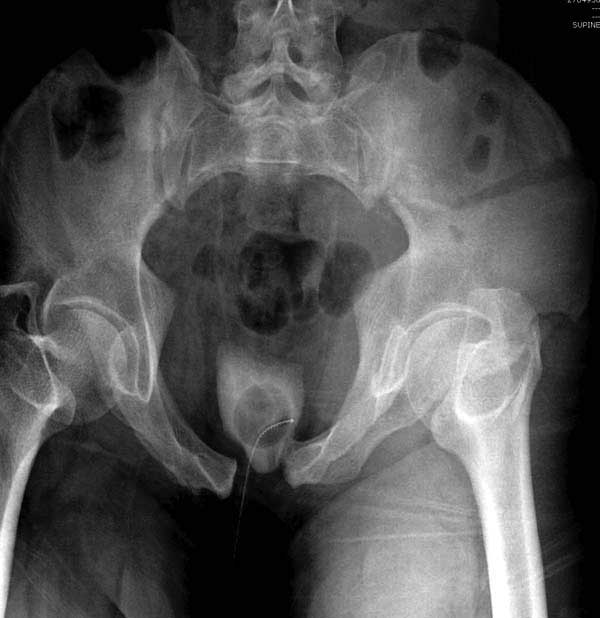

Рецидив смещения - признак несостоятельности фиксации. В первую очередь из-за ранней нагрузки, или когда имеется нестабильность в тазовом кольце. При повреждениях транссакральных структур сзади, фиксация переднего полукольца-симфиза облегчает репозицию, но не гарантирует стабильность. Нестабильное тазовое кольцо ранее или поздно срывает фиксацию симфиза.

Подробное изучение инлет и оутлет, а также КТ срезов, поможет разобраться в диагностике. Без обследования случай усложнится. Операция непростая, кроме технических навыков, надо иметь стандартные инструменты для операции.

Здесь представлен случай 38 летнего больного (падение с высоты 9 метров) с нарушением тазового кольца. При поступлении для стабилизации передне-нижний аппарат наружной фиксации и на 6й день, вчера, операция из двух доступов.